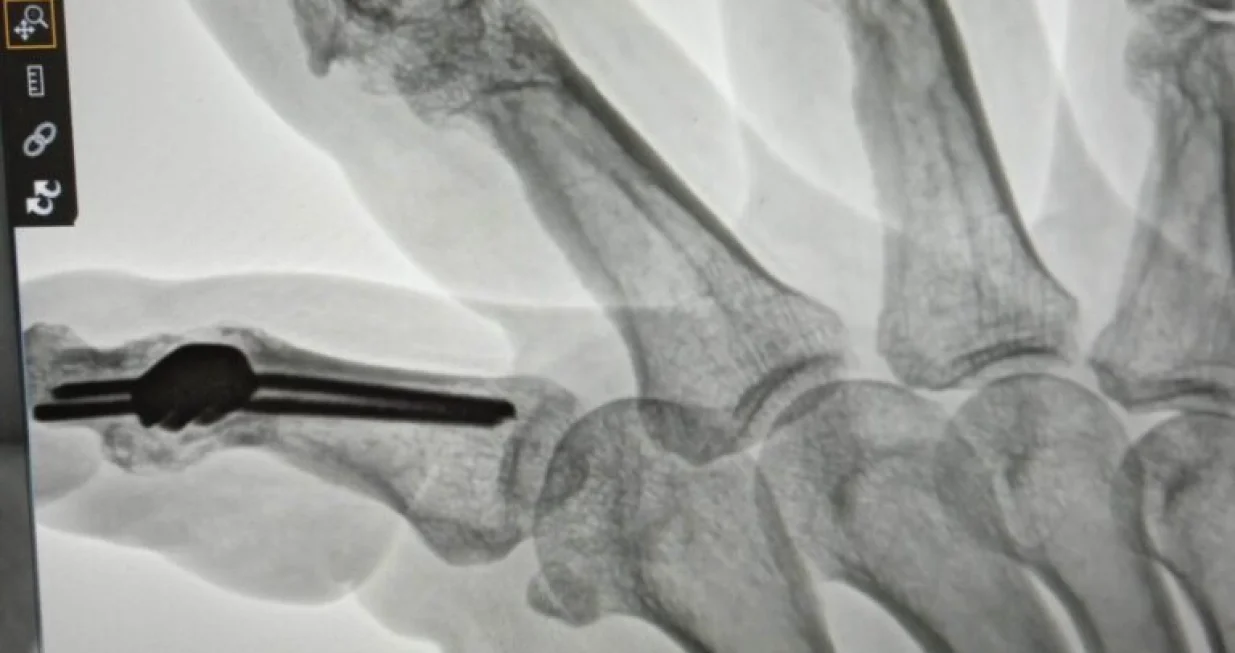

Naime, Andrej je u decembru 1992. godine ranjen na području Otesa i to pet rana odjednom. 1994. se zaputio na liječenje u Sloveniju gdje su mu ugrađeni implanti uz dijagnozu da se svakih 10 godina isti moraju promijeniti, prenosi Hayat.

1994. se zaputio na liječenje u Sloveniju gdje su mu ugrađeni implanti uz dijagnozu da se svakih 10 godina isti moraju promijeniti